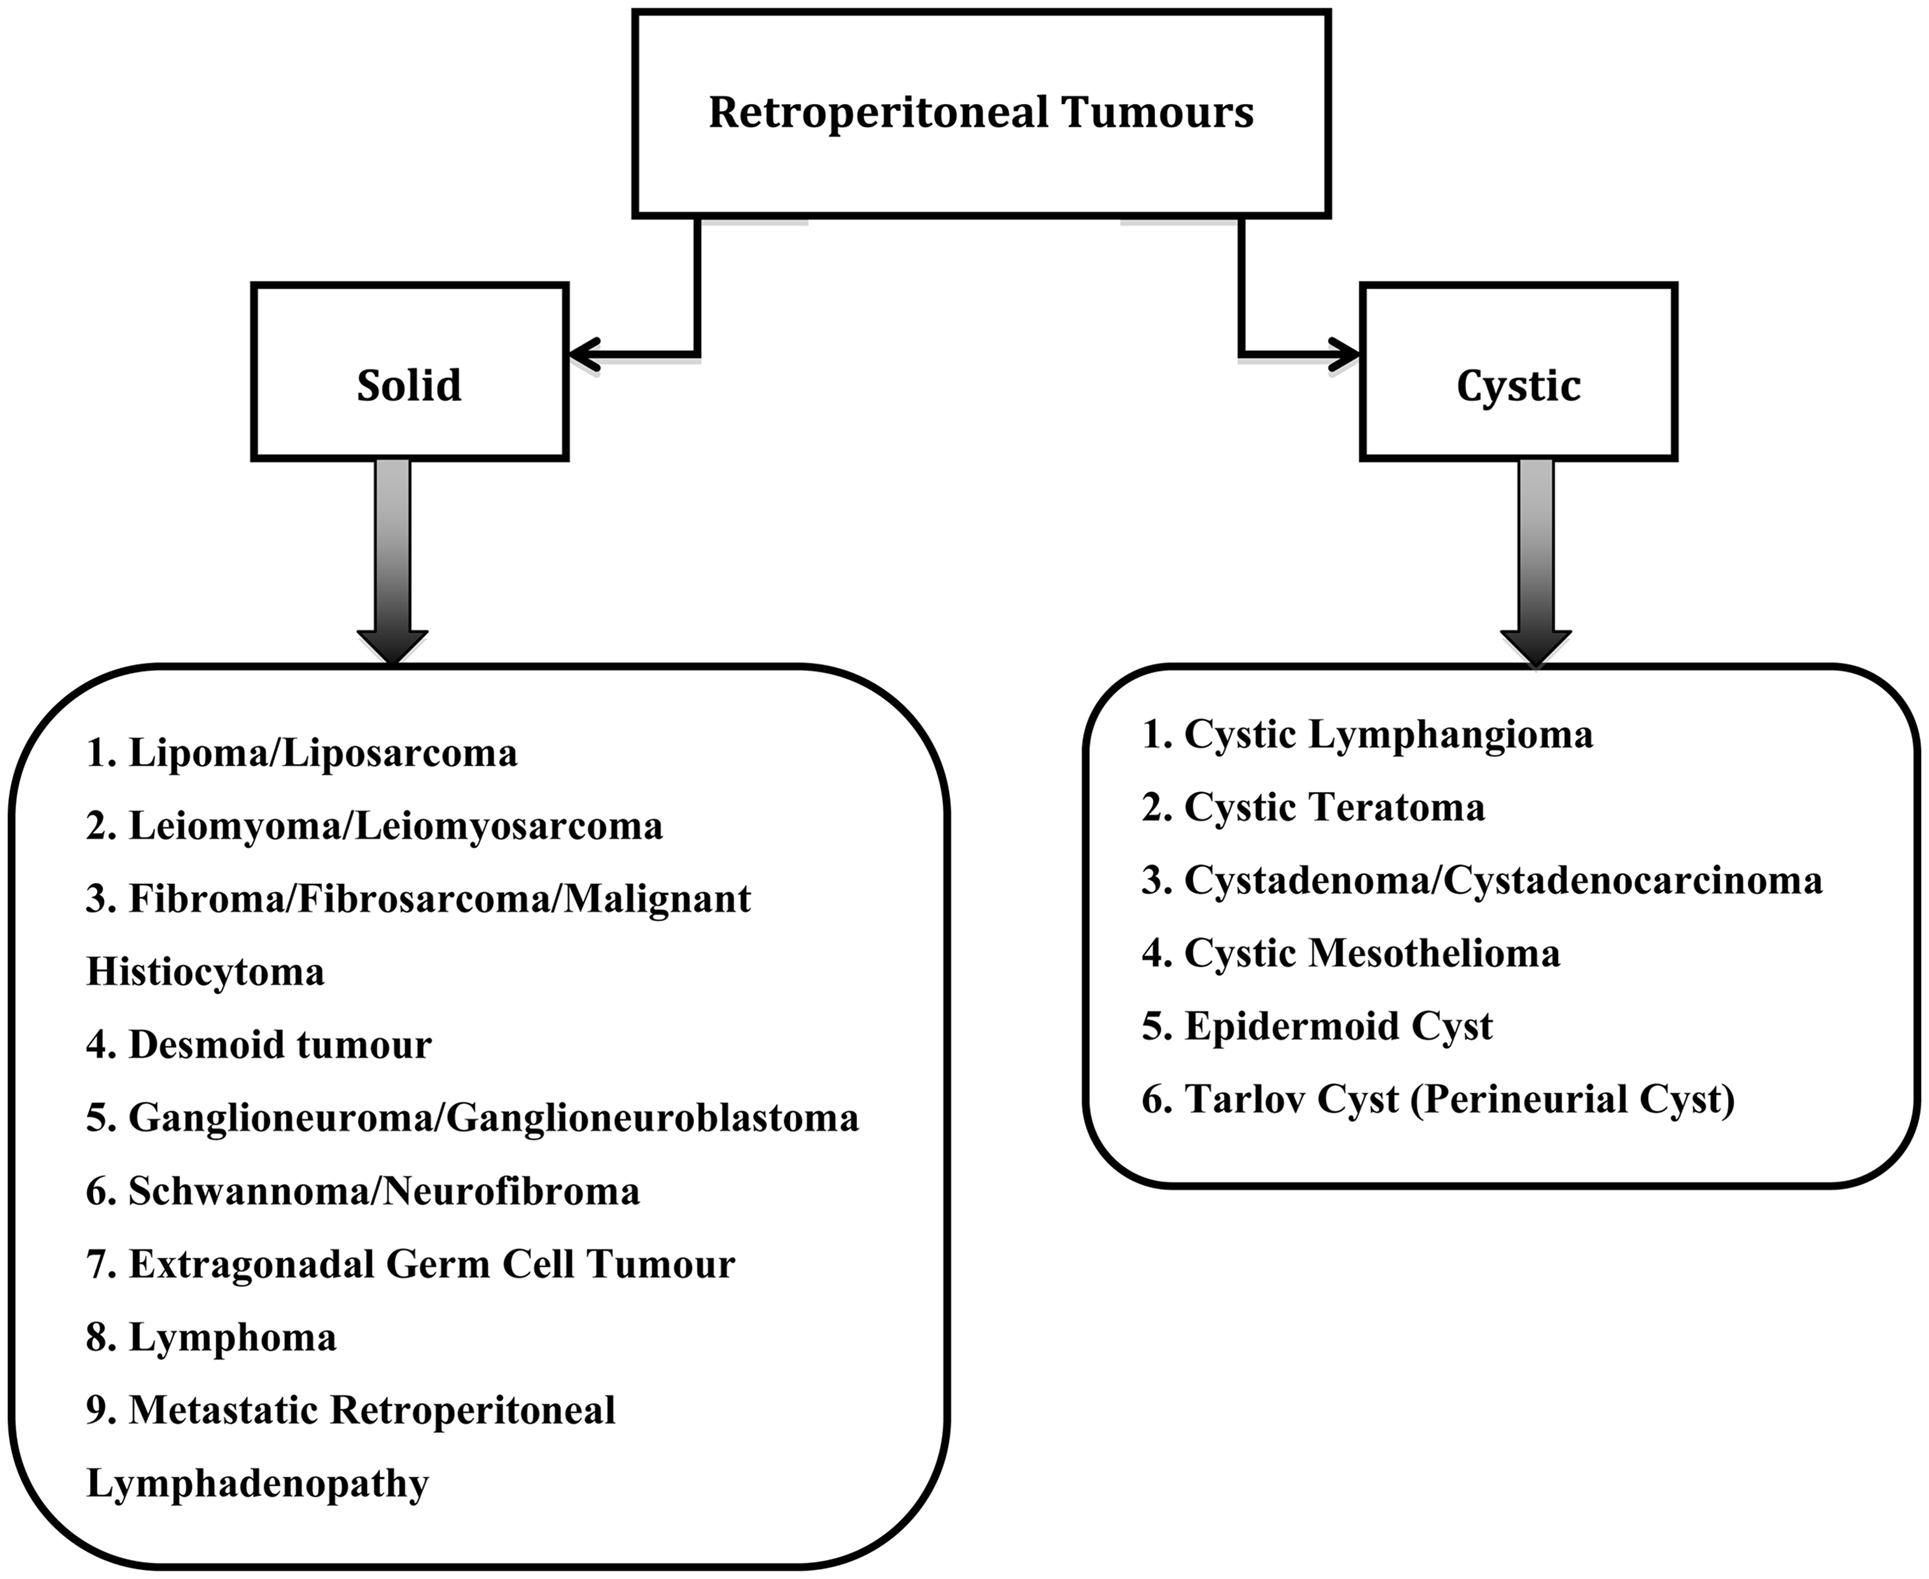

Primary Retroperitoneal Tumors | Radiology Key

radiologykey.com

radiologykey.com

retroperitoneal tumor tumors staging

Frontiers | Retroperitoneal Tumors In The Pelvis: A Diagnostic

www.frontiersin.org

www.frontiersin.org

retroperitoneal tumours tumors frontiersin pelvis gynecology diagnostic challenge types figure fsurg